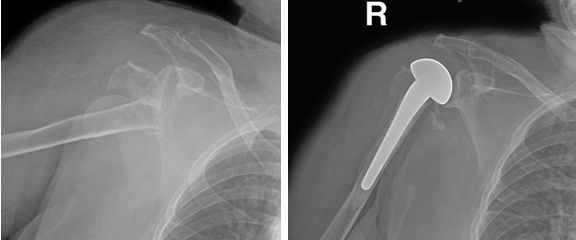

肩关节骨折

病例一:

女性22岁,车祸伤右肱骨近端骨折并肱骨头脱位,行切开复位钢板螺钉内固定手术。

术前                            术后

病例二:

女性83岁,跌倒致右肩关节骨折脱位,行人工肱骨头置换手术。